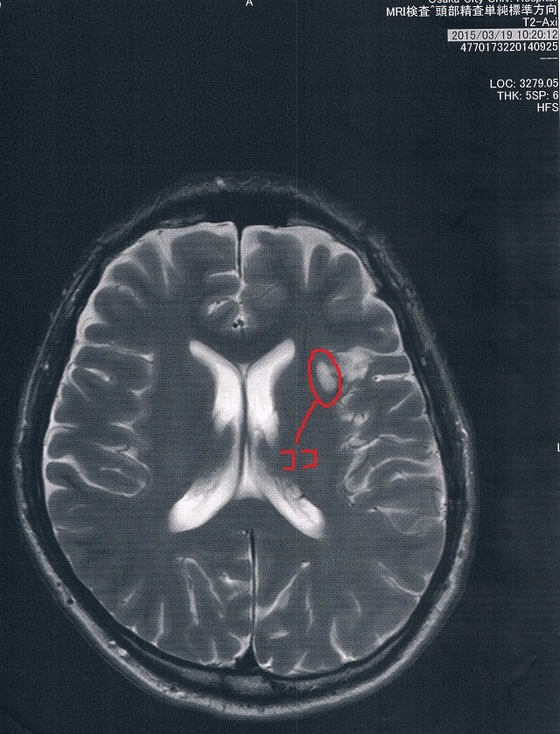

2015/3/19(手術後9か月)のMRI画像

言語中枢の保存のためにあえて取らなかった腫瘍がどうなっているか気になる。

手術時の生検で腫瘍の悪性度が低いことが分かっているけど気になる。